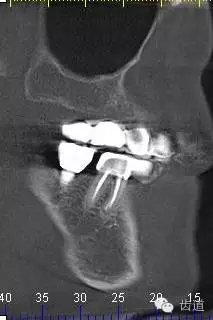

2、45,46術(shù)前片顯示根管上段充填物,根管影像不清晰,少許根尖暗影

5、右下頜側(cè)面觀

6、45,46,47牙片

7、45,46,47CBCT